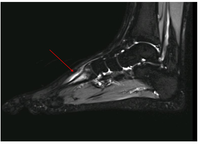

Magnetic Resonance Imaging ‘MRI’ is the most versatile imaging technique used in modern medicine. MRI does not use X-rays or ionising radiation, so it is much safer to use than CT or X-rays. It is also able to produce high-resolution images of all tissue types - bone, muscle, tendon, ligament, cartilage etc, meaning it is very useful in sports medicine.

Recently MRI machines with stronger magnets have been developed - 3 Tesla ‘3T’ MRI is able to produce the highest resolution images, and is particularly useful for ‘Cartilage mapping’, in patients with subtle cartilage injuries.